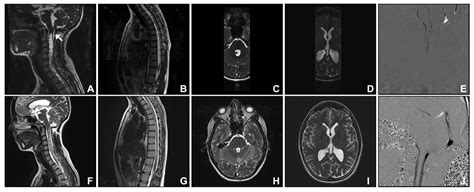

At its core, Cerebellar Tonsillar Ectopia describes the displacement of the cerebellar tonsils into the upper spinal canal. While often used interchangeably with Chiari malformation, it is important to note that the term "ectopia" typically refers to the physical descent of these structures. In many cases, this descent is identified incidentally during imaging studies like an MRI, performed for unrelated reasons such as persistent headaches or neck pain.

The primary concern with this condition is the crowding of the space at the base of the skull. Because the foramen magnum is a rigid, bony ring, any structure occupying space that should be reserved for fluid flow can lead to increased intracranial pressure. The degree of displacement is usually measured in millimeters, and while not every patient with this condition experiences debilitating symptoms, those who do often report complex neurological challenges.

To confirm the presence of Cerebellar Tonsillar Ectopia, physicians rely heavily on high-resolution imaging. The diagnostic process is essential for differentiating between simple ectopia and other structural pathologies. The following table summarizes the primary tools used in evaluation:

Magnetic Resonance Imaging (MRI) Gold standard for visualizing the brain and spinal cord structure.

Cine Flow MRI Analyzes the velocity and volume of cerebrospinal fluid (CSF) flow.

The flow of cerebrospinal fluid is the "pulse" of the central nervous system. It acts as a shock absorber and clears waste products from the brain. In patients with Cerebellar Tonsillar Ectopia, the displaced tonsils may partially obstruct the narrow space where the CSF exits the skull. This blockage can create a bottleneck effect, leading to pressure buildup. When the fluid cannot circulate freely, it may lead to the formation of a syrinx—a fluid-filled cyst within the spinal cord—which can cause further neurological damage if left unaddressed.